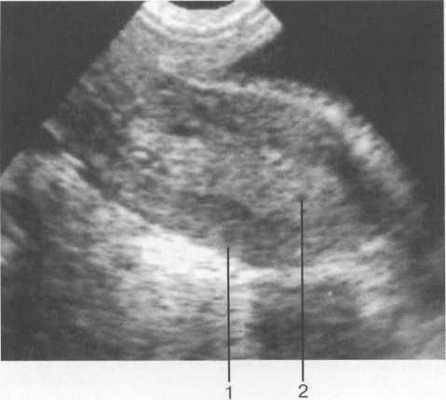

Матка. Дно матки обычно обращено кпереди, образуя с осью шейки открытый угол, составляющий 70—100°. При наполнении мочевого пузыря этот угол увеличивается. В матке выделяют верхнюю широкую часть — тело и нижнюю узкую — шейку. При ТА УЗИ определяют положение матки в малом тазу, ее контуры, структуру тела матки и шейки матки, их длину (продольное сечение), ширину и переднезадний размер (поперечное сечение), оценивают состояние миометрия, эндометрия и эндоцервикса (рис. 15.1).

Рис. 15.1. УЗИ матки, схема.

а — продольное сканирование; б — поперечное сканирование; 1 — матка; 2 — яичники; 3 — М-эхо.